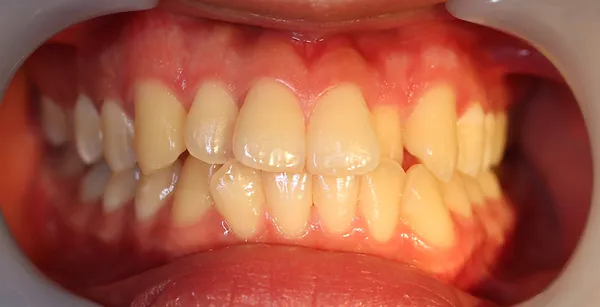

2ホワイトニング【治療例1】

治療前

治療後